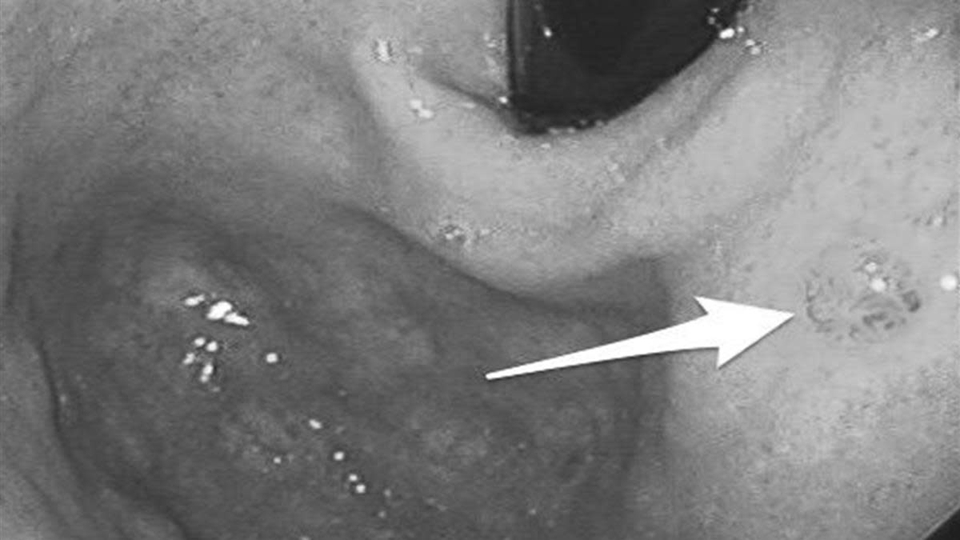

Theo Cơ quan Nghiên cứu UT Quốc tế (IARC), bệnh thường tiến triển qua một quá trình dài: viêm mạn tính, tổn thương niêm mạc, tăng sinh bất thường rồi mới chuyển thành UT.

Cơ chế này chịu tác động của nhiều yếu tố. Nhiễm vi khuẩn Helicobacter pylori (HP), ăn mặn kéo dài hoặc thói quen sinh hoạt thất thường đều có thể làm suy yếu lớp bảo vệ niêm mạc dạ dày. Khi quá trình tổn thương và sửa chữa lặp lại nhiều lần nhưng không hoàn chỉnh, niêm mạc có thể xuất hiện “chuyển sản ruột” – một dạng tổn thương tiền UT.

Các tổng quan trên tạp chí The Lancet Oncology cho thấy nếu can thiệp từ giai đoạn tiền UT, tiên lượng có thể cải thiện hơn 50%. Tuy nhiên, điểm khó là giai đoạn này hầu như không gây đau dữ dội, mà chỉ là những thay đổi nhẹ, dễ bị xem nhẹ.